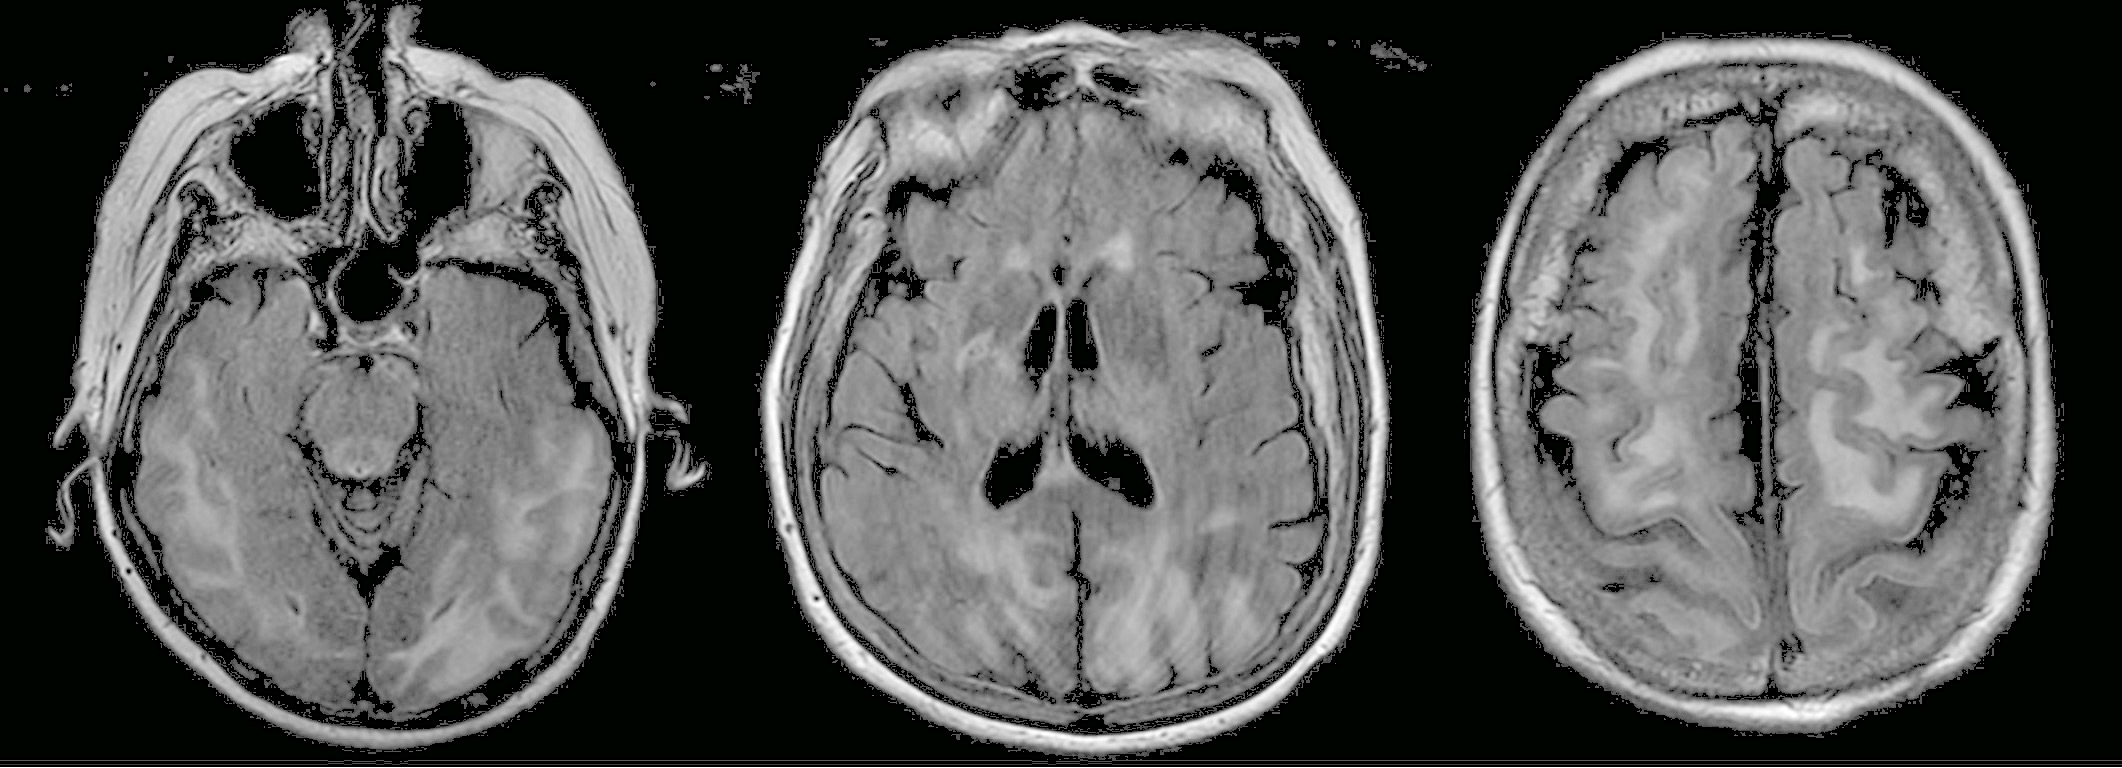

On hospital day 3, MRI with and without contrast revealed an extensive signal abnormality within the white matter of the posterior cerebral hemispheres and frontal lobes, cerebellar hemispheres, and thalami (Figure), a finding most consistent with posterior reversible encephalopathy syndrome (PRES).

Figure. Extensive hyperintense signal was seen on T2-weighted fluid-attenuated inversion recovery MRI images involving the subcortical and juxtacortical white matter of the posterior temporal, occipital, parietal, and frontal lobes in addition to the thalami.

Imaging plays an important role in the diagnosis of PRES. MRI is more sensitive in diagnosing PRES than CT, and the authors of one case series of 30 patients found that 37% presented with negative findings on head CT.11 Therefore, MRI is the preferred imaging modality for diagnosis of suspected PRES.12 Imaging should be implemented early in the evaluation of patients on immunosuppressive agents who present with altered mental status and hypertension. Typical MRI findings consistent with PRES are observed primarily in the parieto-occipital region of the brain; however, atypical presentations often include the frontal lobe, basal ganglia, cerebellum, or temporal lobes.13 Radiologists who note such changes on an MRI should immediately discuss the possibility of PRES with their clinician colleagues so that the patient’s blood pressure may be adequately controlled.